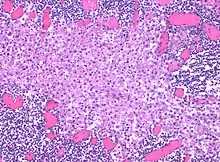

In medicine, histiocytosis is an excessive number of histiocytes[1] (tissue macrophages), and the term is also often used to refer to a group of rare diseases which share this sign as a characteristic. Occasionally and confusingly, the term histiocytosis is sometimes used to refer to individual diseases.